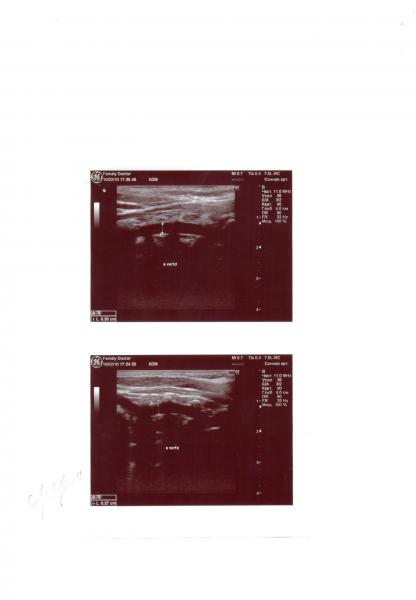

Заключение: непроходимость ПА(слева), изогнута в проксимальном отделе(см. файлы).

- Непрямолинейность хода ПА - сканирование0001_1.jpg (46.32 КБ) 2107 просмотров

- Непрямолинейность хода ПА - сканирование0004.jpg (14.59 КБ) 2107 просмотров

Дробрый вечер, прочитать описание по фотографии не смогла, слишком мелко.Теоретически если артерия непроходима по какимто причинам, надо оценивать состояние коллатерального кровотока и смотреть насколько он компенсирует непроходимость. А после травмы потеря сознания - обычное дело, ничего в этом выдающегося нет. Будьте внимательны и больше не падайте.Таня+Майя:Здравствуйте, Кетеван.Дочери 4 года. Сделали УЗИ брахиоцефальных артерий(после сильного ушиба головой(было 3 раза всего), теряет сознание на 2-3 секунды(как-будто её выключают), я её тормошу, дочка приходит в себя - плачет). Заключение: непроходимость ПА(слева), изогнута в проксимальном отделе(см. файлы).Скажите, пожалуйста, чем это чревато кроме потери сознания при ушибе головы? Что противопоказано(вид спорта, перелёты), показано?Спасибо.С уважением, Татьяна.